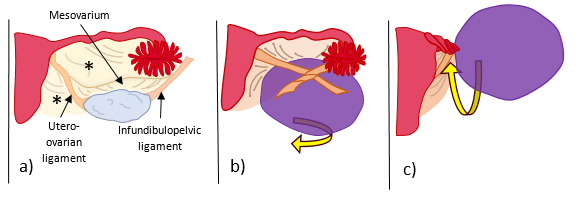

Ovarian torsion is an uncommon cause of acute pelvic and abdominal pain, with an overall estimated incidence of 2-3% of gynaecologic emergencies1. It results from twisting of the ovarian vascular pedicle, leading to partial or complete blood flow obstruction with venous, arterial, and lymphatic stasis. The Fallopian tube often twists along with the ovary, in which cases it is referred as adnexal torsion2,3 (Fig. 1). It is a surgical emergency since treatment delay leads to haemorrhagic infarction, which may ultimately evolve to ovarian necrosis with subsequence autoamputation or superinfection4,5.

The most common predisposing factor is an underlying ovarian mass, usually greater than 5 cm, that weights the ovary down and induces it to rotate on the axis of the infundibulopelvic and utero-ovarian ligaments (Fig. 1).

Figure 1: Schematic illustration of a) normal anatomy of the ovarian ligaments: infundibulopelvic ligament (or suspensory ligament of the ovary), which is a fold of the broad ligament (*) that contains the ovarian vessels and is attached to the pelvic sidewall, the utero-ovarian ligament (or proper ovarian ligament) which attaches the ovary to the lateral wall of the uterus, and the mesovarium which attaches the ovary to the broad ligament (*); b) ovarian torsion with twisting around the infundibulopelvic and utero-ovarian ligaments, and c) adnexal torsion with twisting of the Fallopian tube along with the ovarian ligaments.